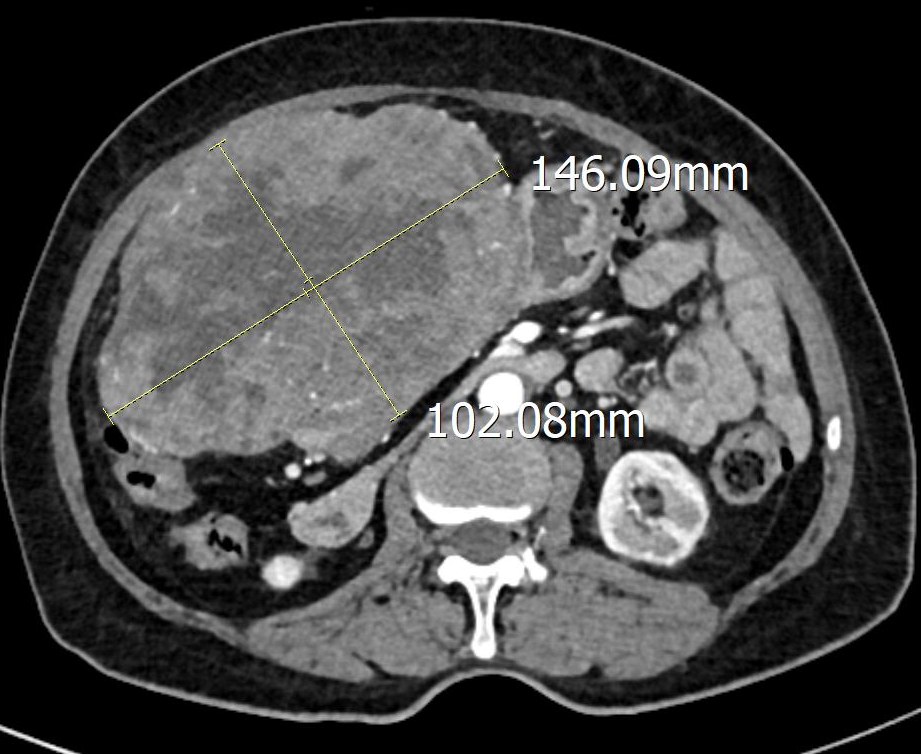

三年前,文婆婆在体检时发现胃部有一大小约2.5cmx2.4cm的包块占位,没有任何的不适,故未引起重视。一个月前,文婆婆发现肚子变大,并且摸到了一个大包块,还经常有黑便,多次出现头晕眼花乏力等症状。为了搞清楚病因到我院普通外科就诊,经完善CT提示腹腔巨大占位性病变,大小约14.7x9.6x15.7cm。

腹部CT

通过CT图像清楚发现肿瘤已经明显增大,在完善相关辅助检查后,发现文婆婆还存在严重的贫血,粪便隐血呈强阳性,这一切都提示肿瘤正在出血。